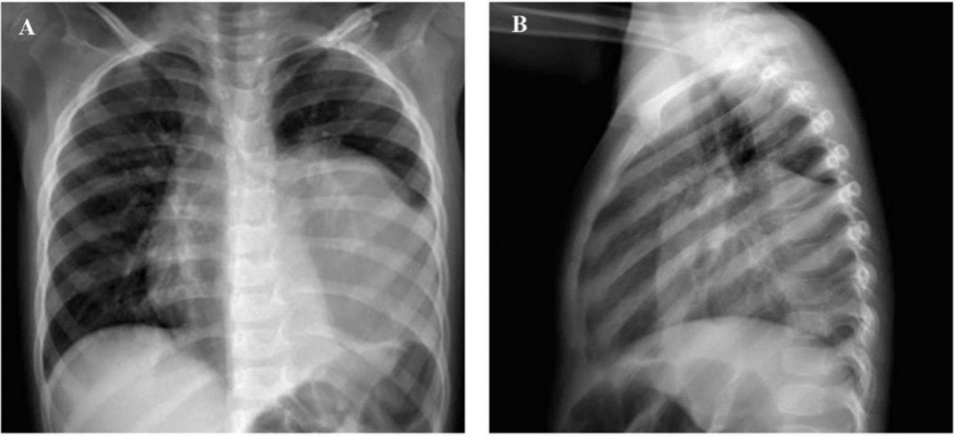

Three-year-old girl with no significant personal or family history, attended with her father, who reported that the patient presented clinical symptoms characterized by pain in the mesogastrium since 6 months ago, to which she did not pay attention, a week ago the pain intensified accompanied by nausea that did not lead to vomiting. On physical examination, on deep palpation in the mesogastrium there is evidence of a mass of hard consistency, well-defined borders of approximately 3cm in diameter, non-mobile. An abdominal ultrasound was sent and reported a complex mass in the pancreas, round edges, slightly heterogeneous content, negative Doppler, measuring 8.9x7.9x9.6cm. Due to limited resolution capacity, the patient was referred to a more complex health care facility, and the clinical picture was accompanied by a wet cough and an unquantified thermal rise. Chest X-ray reports blurring of the left costo-diaphragmatic angle, blurring of the cardiac silhouette due to the presence of radiopacity in the left hemithorax (Figure 1). CT Scan of the Chest with Contrast and upper abdomen shows a solid mass that captures contrast and with vessels inside, located in the left pleural cavity measuring 8.1cm x 11.2cm x 8.2 cm (width x height x depth) with a volume of approximately 387cc (Figure 2). Due to the complexity of the lesion she was referred to pediatric cardiothoracic surgery where she underwent exploratory thoracotomy obtaining a complete exeresis of the mediastinal mass without complications. A sample was sent for histopathological study which was compatible with ganglioneuroma. The patient was continuously monitored in the pediatric intensive care unit and was successfully discharged after 15 days.

Figure 1 Chest X-ray. (A) Posteroanterior projection (B) Lateral projection.